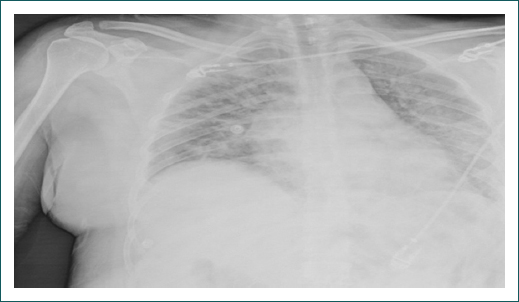

En los exámenes de laboratorio a su ingreso destacaba: leucocitosis (16.94 celulas/microlitro [cel/mL]), neutrofilia (15.96 cel/mL), linfopenia (0.53 cel/mL) y elevación de la lactato deshidrogenasa (380 unidades/litro); la PaO2/FiO2 era de 128 y la SpO2/FiO2 de 240 (Cuadro I). La radiografía de tórax inicial mostró infiltrados intersticiales bilaterales, periféricos, hacia ambas bases (Fig. 1).

La paciente presentó disminución de la saturación de manera progresiva, llegando a una SpO2 de 84%; la frecuencia respiratoria se mantuvo entre 20-28 rpm (Fig. 2). En este contexto, por hipoxemia persistente, se realizó maniobra de pronación en paciente no intubada con mejoría a los 10 minutos y elevación de la saturación de oxígeno por pulsioximetría hasta 94% (Fig. 3). Esta posición se mantuvo cuatro horas por tolerancia de la paciente. Al encontrar mejoría, se indicó repetir posición prono dos veces al día de cuatro a ocho horas (según tolerancia de la paciente), por cuatro días en total. La paciente presentó mejoría clínica, por pulsioximetría y en la relación PaO2/FiO2, que en supino alcanzó 285 al tercer día posterior a la pronación (Cuadro I). Se realizó nueva PaO2/FiO2, posterior al cuarto día de posición prono con un resultado de 332, y nueva radiografía de tórax tres días después de la maniobra de posición prono, la cual mostró disminución de los infiltrados intersticiales bilaterales (Fig. 4). Se retiró el oxígeno suplementario con SpO2 de hasta 94% al aire ambiente, sin requerimiento de oxígeno suplementario y con una SpO2/FiO2 de 447. Se realizó prueba de caminata de seis minutos con disminución de la SpO2 de 94% a 92%. Se indicó su egreso a los ocho días de hospitalización con signos vitales estables.